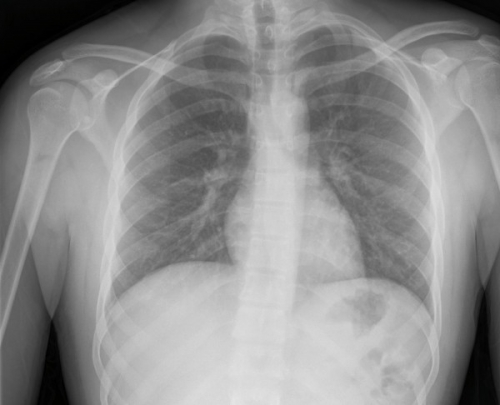

Tool to train medical student's eyes as to what a normal chest x-ray looks like, with over 500 consecutive normal images.